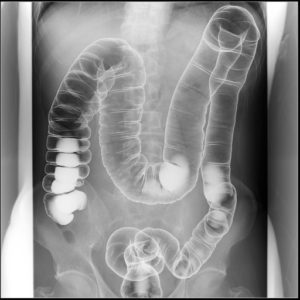

潰瘍性大腸炎(左側結腸炎型)で通院している54歳女性の症例を見てみましょう。便秘と頻尿を訴えていたため、腹部単純X線を撮影しました上行結腸、盲腸には多量の便が貯留していて、盲腸は骨盤内の正中にまで達しています。本症例はCTの撮影はしていないのですが、便がたまった盲腸が膀胱を圧排していそうな状況が見て取れます。この患者には下剤を処方し、排便が改善、同時に頻尿を訴えることもなくなりました。

上のレントゲンはお腹の写真です。

Cが大腸の始まり盲腸(回盲部)、Aは上行結腸、本来であれば便が溜まっている場所ではありません。

慢性的な便秘のため大腸全体に便が詰まってしまっています。